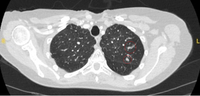

Computed tomography (CT) sections with examples of semi-solid solitary nodules

From the collection of Dr George Tsaknis, MD, PhD, FRCP(London), MRQA, MAcadMEd, PGCert; used with permission